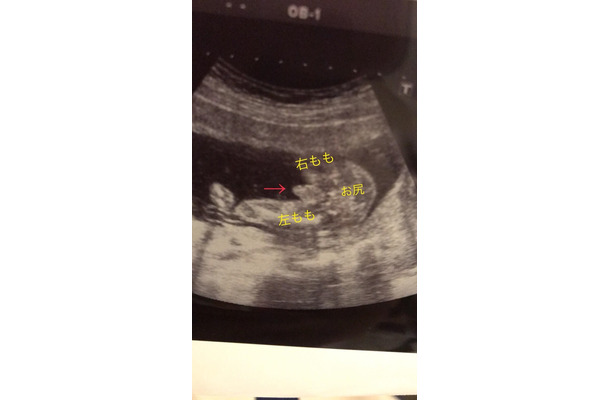

ブログには赤ちゃんのお尻を下から撮ったエコー写真を公開。お尻と太ももの位置を説明し、「おおおおおお!! ハッキリと……(笑)2人目は男の子の予定です」と報告した。

自身初となる男児の妊娠に河内は「自分のお腹の中に男の子がいると思うとなんだかすごい不思議な気持ち 早くも胎動がすごいのでやんちゃな子なんだろうな~早く会いたい でもまだまだお腹の中で立派に成長してね!」と締めくくっている。